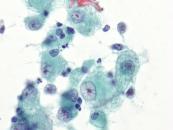

第35回日本臨床細胞学会九州連合会学会(宮崎)スライドカンファレンス症例2

種別:消化器・口腔

出題:佐賀大学医学部 病因病態科学講座 臨床病態病理学分野 力武 美保子 先生

| 年齢 | 60歳代 | 性別 | 女性 |

| 採取部位 | 肝内胆管(B5) | 採取方法 | ENBDチューブより採取した胆汁 |

既 往 歴:6年前に進行大腸癌に対し、右半結腸切除術後。

現 病 歴:大腸癌の術後フォロー中に肝内胆管(B5,B4)の拡張を認めた。精査目的にERCPが行われ、B5にENBDチューブが留置された。

| 正解 | 3.腺癌(大腸癌の転移) |

▼選択肢及び投票結果

| 1.肝内結石症 | 1件 | (1.0%) | |

| 2.腺癌(胆管細胞癌) | 36件 | (37.1%) | |

| 3.腺癌(大腸癌の転移) | 37件 | (38.1%) | |

| 4.IPNB | 5件 | (5.2%) | |

| 5.腺扁平上皮癌 | 18件 | (18.6%) | |

| 投票総数 | 97件 | (100%) |